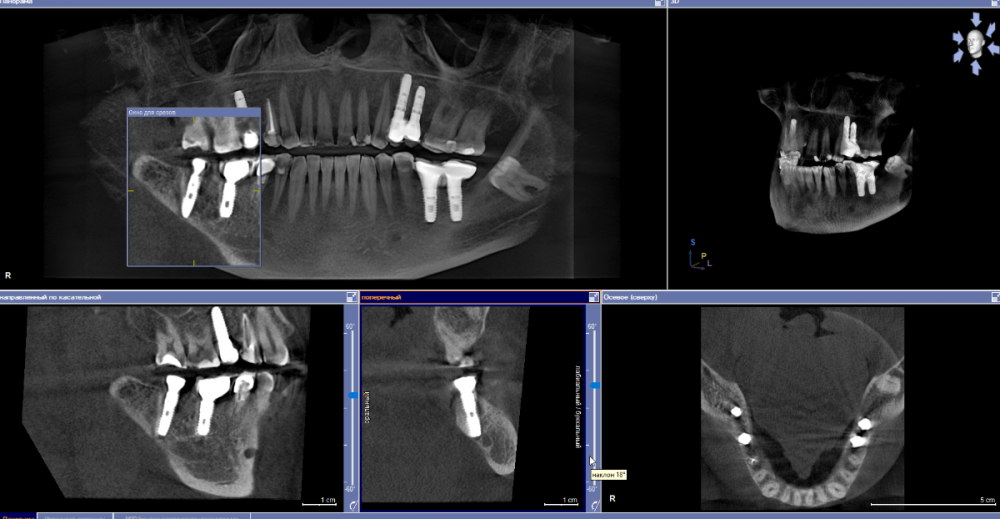

se77777 Опубликовано 3 апреля, 2023 Автор Поделиться Опубликовано 3 апреля, 2023 Здравствуйте, проведена одномоментная имплантация. Спустя 5 месяцев поставлена коронка. Коронка стоит месяц. На третьем месяце после имплантации стала беспокоить боль в плече, списывал на перенесенный COVID-19. Было субъективное ощущение, что температура формирователя повышена по отношению к остальным зубам и к формирователям, которые носил прежде. На днях стали беспокоить тянущая неинтенсивная боль в челюсти со стороны импланта. КТ сделана полтора месяца назад. Ссылка на комментарий

red_butler Опубликовано 3 апреля, 2023 Поделиться Опубликовано 3 апреля, 2023 Здравствуйте, срезы кт выставлены не правильно. Покажите еще Ссылка на комментарий

АнтонТЛТ Опубликовано 4 апреля, 2023 Поделиться Опубликовано 4 апреля, 2023 У нижних двух окошек есть ползунки слева. Оси нужно выставить параллельно имплантату 1 Ссылка на комментарий

se77777 Опубликовано 5 апреля, 2023 Автор Поделиться Опубликовано 5 апреля, 2023 Спасибо. Ссылка на комментарий

red_butler Опубликовано 5 апреля, 2023 Поделиться Опубликовано 5 апреля, 2023 по Кт все нормально, нужно смотреть очно 1 Ссылка на комментарий